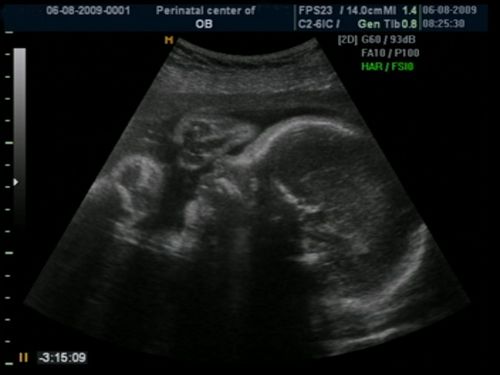

Инструментальная диагностика

Состояние беременности можно оценить с помощью ультразвукового исследования. Во время процедуры специалист сможет выяснить, присутствует ли сердцебиение плода, а также соответствует ли его размер сроку беременности и другим важным параметрам. Кроме того, выполняется анализ крови на уровень ХГЧ, который начинает снижаться, если беременность прекращается (за исключением редких случаев, когда плодные оболочки продолжают развиваться). Гинекологический осмотр также необходим для выявления изменений в размерах матки.

Замершая беременность — это состояние, при котором эмбрион или плод перестает развиваться, но остается в матке. Диагностируется она обычно на ранних сроках с помощью ультразвукового исследования, которое показывает отсутствие сердцебиения или несоответствие размеров плода сроку беременности.